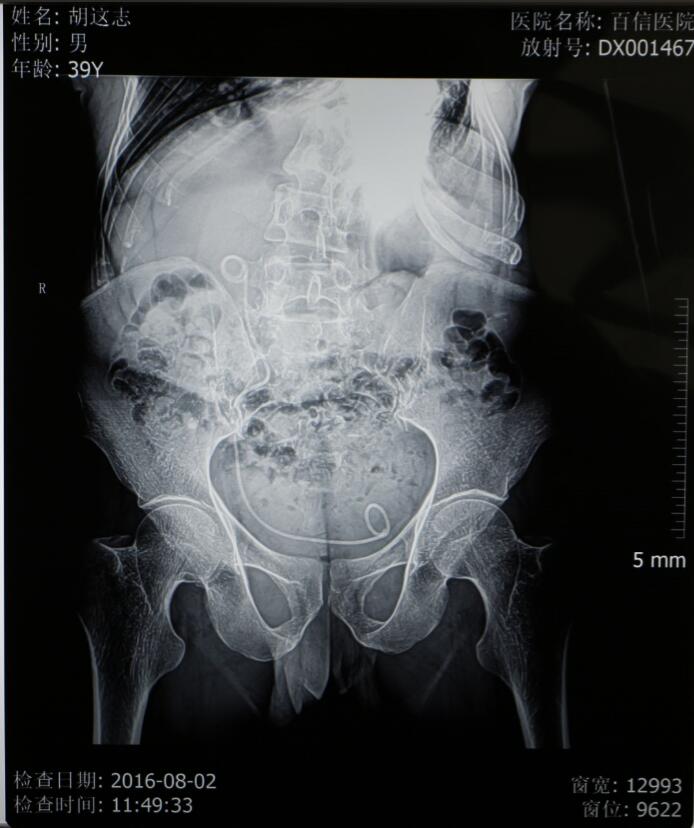

可这些也仅是体表上的显现,当丁主任拿到检查结果时更是不免心头一紧——肌酐、尿素、尿酸等指标均超出正常指标数倍,已经开始呈现出尿毒症的检验结果及体征。患者的左肺已经从身体的右侧胸腔挤压到左侧胸腔,左侧肺功能已经有效消失,同时右侧肺功能也受到了影响,肺活量不到正常人的一半,呼吸很浅很快,并伴有呼吸性酸中毒,并且心脏功能很不好,平时还需要用药物来保持心率;但更加严重的是患有结石的输尿管严重畸形,他的输尿管严重扭曲,左侧输尿管已蜿蜒扭转到身体右侧,从右侧延至膀胱。检查结果显示患者结石的位置还偏偏位于左侧输尿管上段,这也就意味着如果进行手术,则需要将输尿管镜一直蜿蜒延伸到输尿管的尽头才能进行,这些都使手术难度大幅度增加,在从医三十多年,临床经验非常丰富的丁主任看来,这个病例也是非常棘手的。

8月2日是胡先生到医院进行术后拔管的日子,鉴于胡先生的家庭生活状况,院方决定免除拔管手术的所有费用,为胡先生免费进行后续手术,并为胡先生买好了回程的火车票,让胡先生能够更加安心的回家。胡先生此时没有说一句话,但是那颤抖的双手和眼中的泪光足以表达出他内心的感激之情……